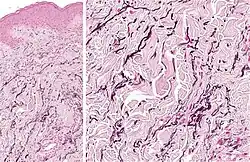

![]() Subcutaneous tissue from a young rabbit. Highly magnified. (Elastic fibers labeled at right) | |

Elastic fibers (or yellow fibers) are an essential component of the extracellular matrix composed of bundles of proteins (elastin) which are produced by a number of different cell types including fibroblasts, endothelial, smooth muscle, and airway epithelial cells.[1] These fibers are able to stretch many times their length, and snap back to their original length when relaxed without loss of energy. Elastic fibers include elastin, elaunin and oxytalan.